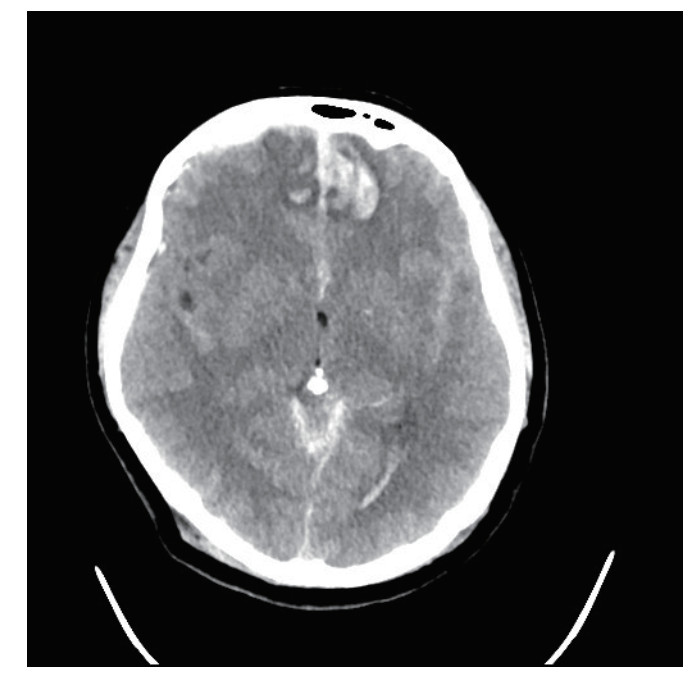

1 病例资料患者,女性,40岁,因“车祸致全身多处外伤半小时余”于2025年6月27日由120送入黄山市人民医院急诊。患者2 h前骑电瓶车发生车祸,致头面部、胸部及左下肢严重受伤,当即昏迷,伴恶心呕吐。入抢救室时自主呼吸微弱,后出现室速,伴随血流动力学不稳定,GCS评分为6分(E1V1M4),双侧瞳孔不等大、对光反射迟钝,左侧直径3 mm,右侧5 mm,后枕部头皮血肿,左下肢胫腓骨区域明显肿胀畸形。医院立即实施全面评估,经紧急行电复律、利多卡因静推后恢复自主心率,予以气管插管保护气道,建立深静脉通路泵入血管活性药物维持血压、纠正酸中毒。完善CT检查:双侧脑挫伤、创伤性蛛网膜下出血、右侧额顶部硬膜下血肿,中颅底及枕骨骨折、累及枕骨大孔,左侧胫腓骨骨折及双肺坠积性改变。见图 1,2。神经外科会诊诊断为弥漫性轴索损伤,无立即手术指征,收入EICU监护稳定生命体征。

| 图 1 脑挫伤伴出血 |